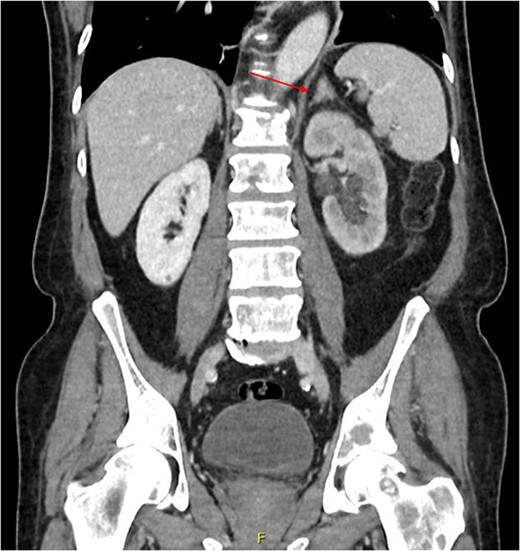

Computed tomography (CT) of the thorax, abdomen and pelvis was requested for staging. Lymphadenopathy was present superior and inferior to the diaphragm, left-sided hydronephrosis with reduced enhancement of the left kidney and widespread mixed lytic and sclerotic lesion affecting the skeleton. The bulky left adrenal gland was concerning for adrenal metastasis (Fig. 3). There was also abnormal urothelial enhancement in the left distal ureter for 4 cm, raising the suspicion of urothelial malignancy (Fig. 4). Blood tests showed a normal prostate specific antigen, mild acute kidney injury, CA19–9 of 17 256 and a carcinoembryonic antigen of 18.

Coronal CT abdomen and pelvis scan with contrast demonstrating urethral enhancement for a distance of 42.8 mm.